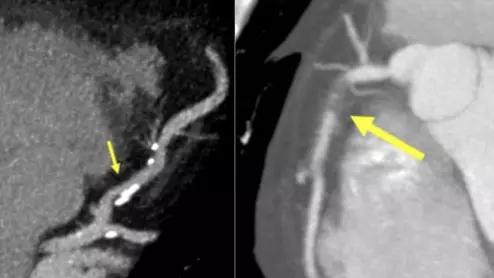

Tim Szczykutowicz, PhD, associate professor radiology, University of Wisconsin Madison, explains the new technology developments in GE HealthCare's  FDA 510(k)-pending photon-counting CT scanner.